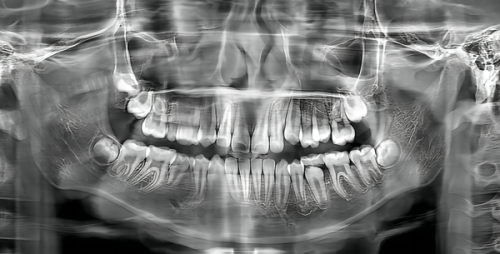

在口腔修复领域,二氧化锆烤瓷牙因其出色的美观性、耐用性和生物相容性,成为越来越多牙体缺损、变色或畸形患者的理想选择。而“二氧化锆烤瓷牙费用多少”也成为患者询问时更关注的问题之一。2025年全新市场数据显示,二氧化锆烤瓷牙的单颗费用普遍在2000-5000元之间,具体价格受材质纯度、医院等级、医生技术、地域差异等多重因素影响。对于注重牙齿美观与功能双重需求的人群来说,了解费用构成及背后的价值逻辑,不仅能避免盲目消费,更能选到性价比更高的修复方案。本文将从2025年全新价格行情出发,详细解析影响费用的核心因素,对比其容貌与功能优势,并提供实用的费用规划建议,帮助读者全方面解答“二氧化锆烤瓷牙费用多少”的疑惑。